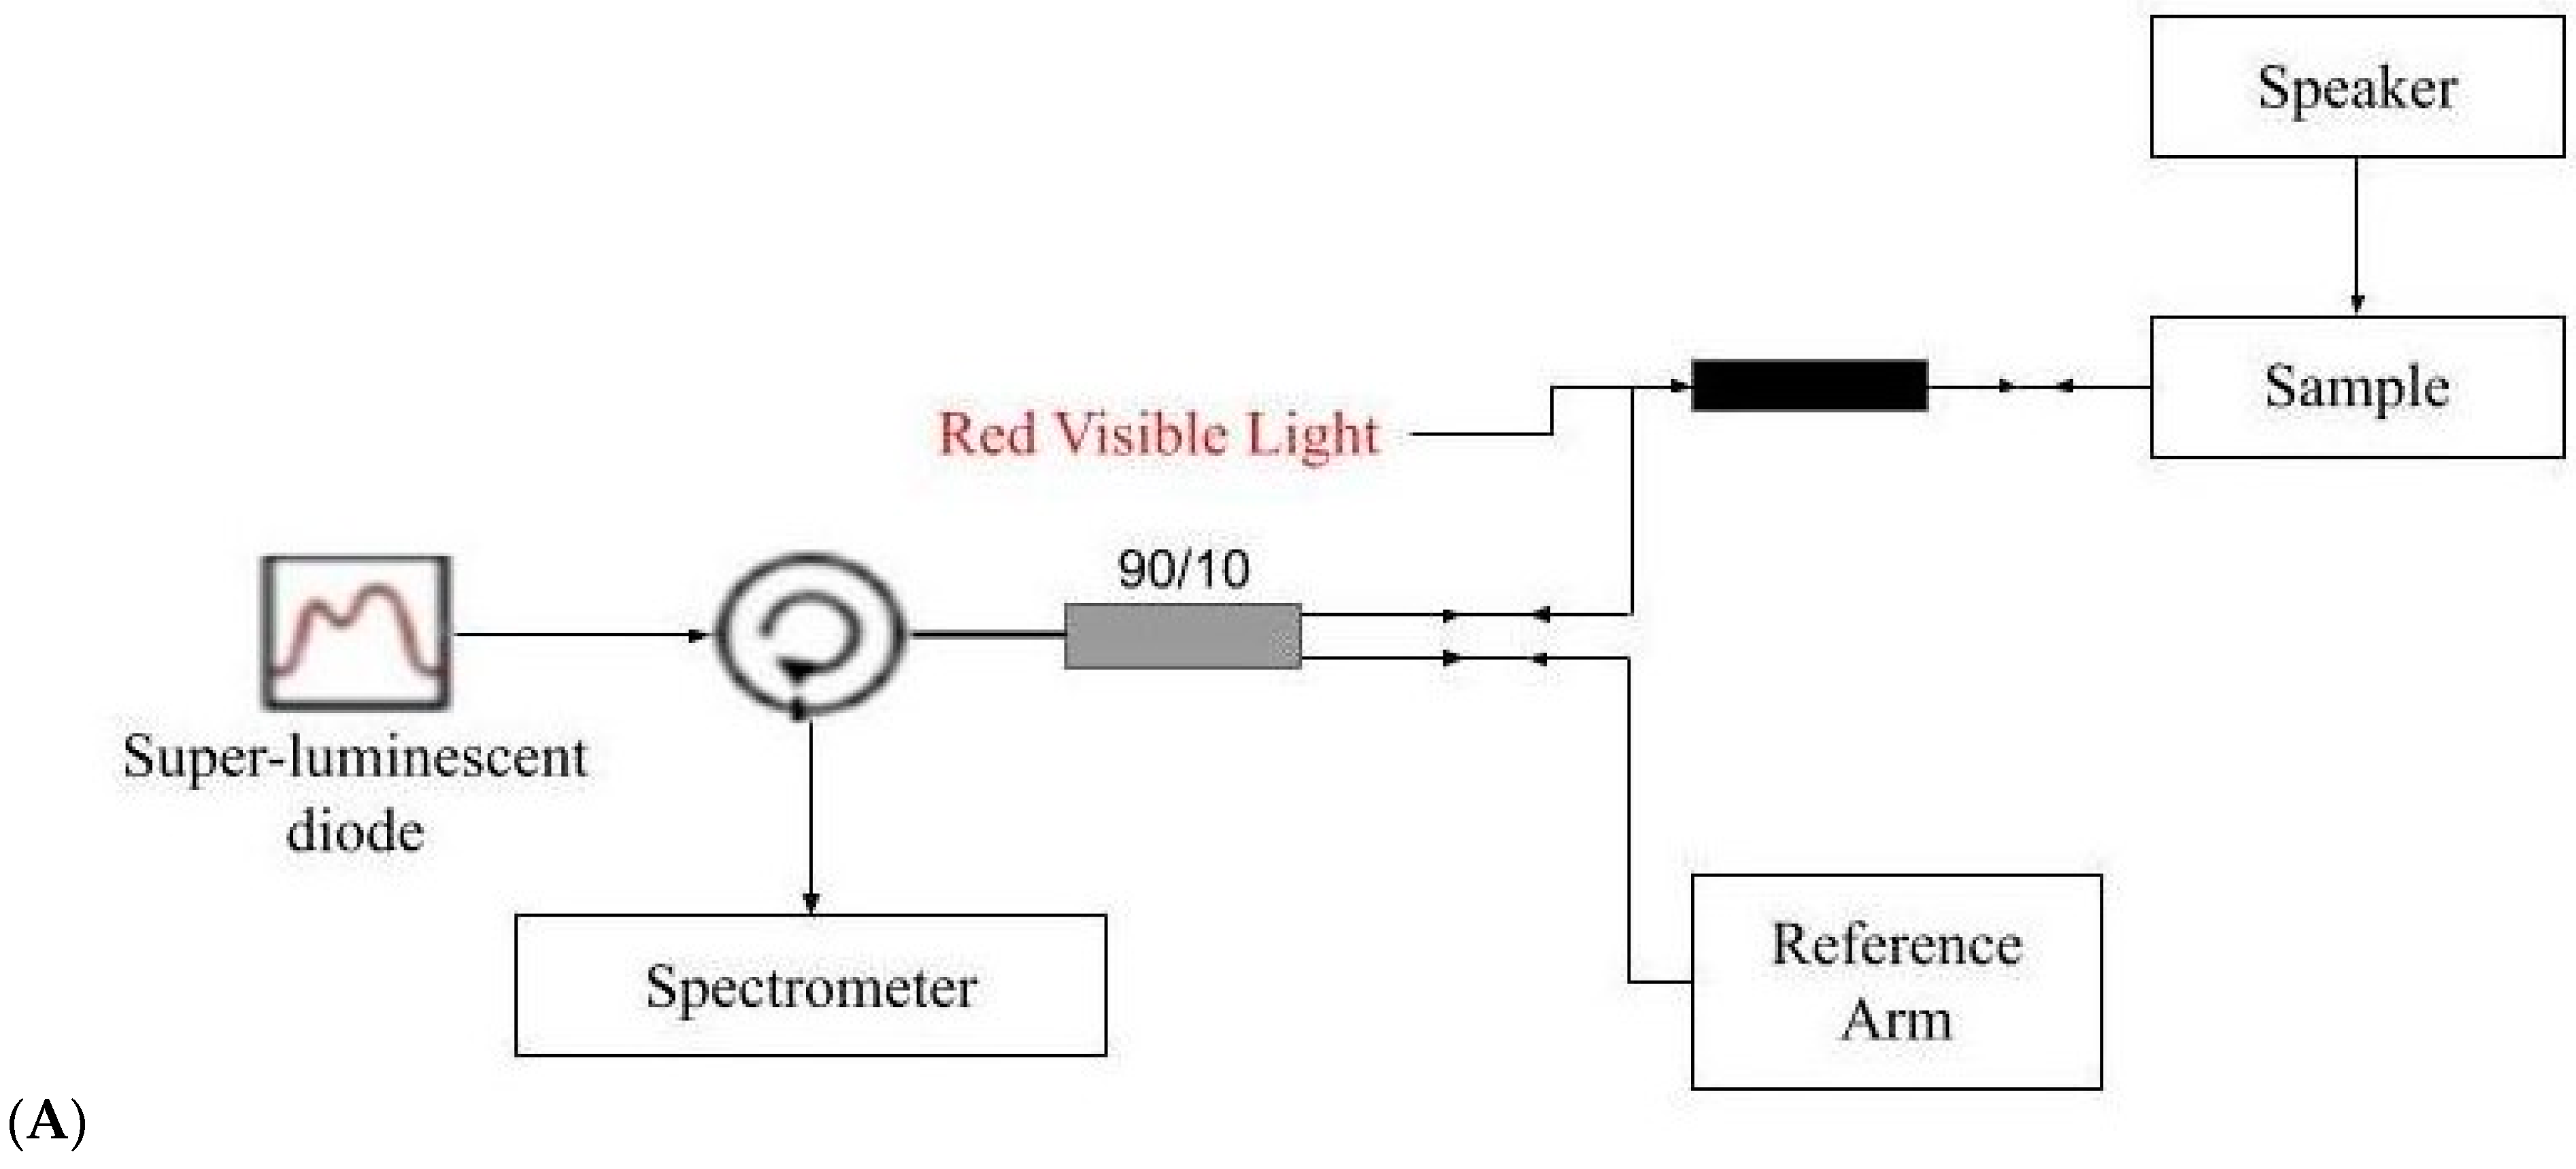

2.2. OCT Images and Scans of Pixel Intensity Versus Depth Measurements

2.3. Measurement of Resonant Frequency and the Elastic Modulus